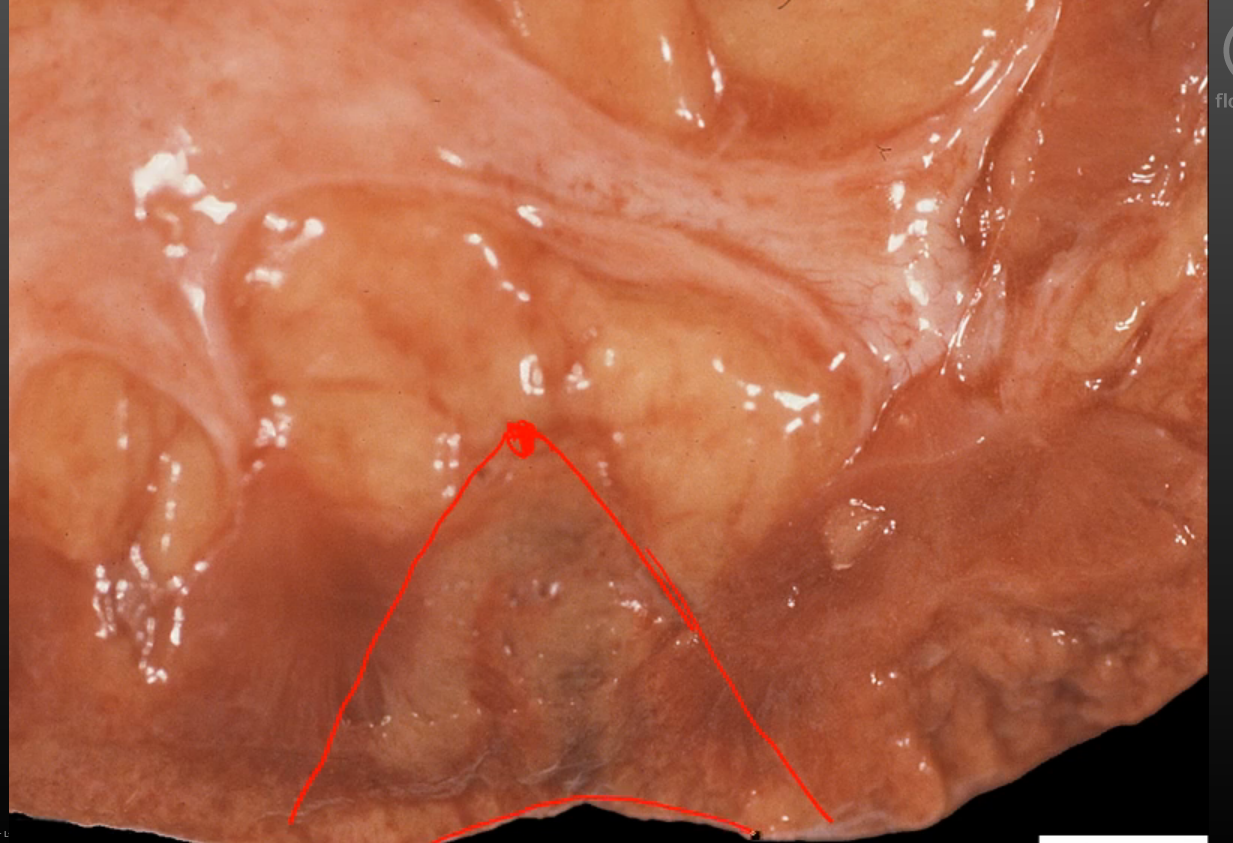

What type of necrosis is indicated by this picture?

Coagulative necrosis 2/2 ischemic infarct- see wedge-shaped pale area of infarction

(a) Ischemic infarct of any tissue besides the brain causes coagulative necrosis

- wedge shaped b/c of the way vessels branch (so obstruction at tip of the wedge causes necrosis in a wedge shape pattern outwards)